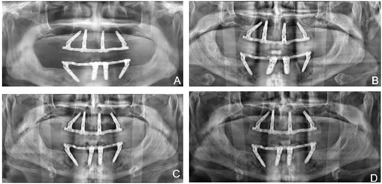

(5)术后复查:术后1个月、5个月复诊,上下颌过渡义齿咀嚼功能较戴用可摘义齿明显改善,面型及发音正常。X线全颌曲面体层片显示种植体骨结合良好(图10)。

种植修复后1、2、4年随访X线全颌曲面体层片显示种植体周围骨结合良好(图13A~C),患者对修复体美观及咀嚼功能效果满意。修复后6年(2022年8月)随访X线全颌曲面体层片及根尖片显示种植体周骨结合良好,上前牙区种植体颈部骨吸收约1 mm(图13D、图14)。取下上下颌义齿,清理义齿组织面滞留菌斑,清洁复合基台并检查基台中央螺丝稳定,清洁义齿组织面,戴回上下颌义齿(图15)。患者口腔卫生宣教,指导正确刷牙,使用冲牙器冲洗义齿与牙龈间缝隙,嘱6个月复查、维护。